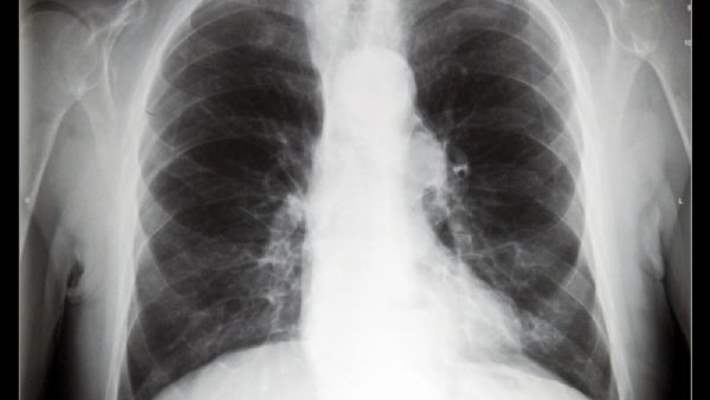

Göğüs röntgeni

Bu ameliyatsız test, kalp ve akciğerlerinizin görüntüsünü bir film üzerinde gösterir. Röntgenler akciğer embolisini tespit edemese ve hastada akciğer embolisi olduğu halde normal çıksa bile, hastalık belirtilerinin aynısına sahip olan diğer hastalıkların elenmesinde önemli bir rol oynar.